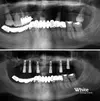

Implant tedavisi